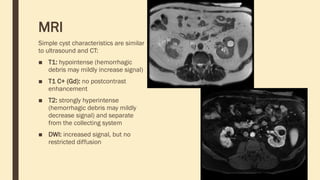

MRI

Simple cyst characteristics are similar

to ultrasound and CT:

■ T1: hypointense (hemorrhagic

debris may mildly increase signal)

■ T1 C+ (Gd): no postcontrast

enhancement

■ T2: strongly hyperintense

(hemorrhagic debris may mildly

decrease signal) and separate

from the collecting system

■ DWI: increased signal, but no

restricted diffusion

MRI Simple cyst characteristicsare similar to ultrasound and CT: ■ T1: hypointense (hemorrhagic debris may mildly increase signal) ■ T1 C+ (Gd): no postcontrast enhancement ■ T2: strongly hyperintense (hemorrhagic debris may mildly decrease signal) and separate from the collecting system ■ DWI: increased signal, but no restricted diffusion